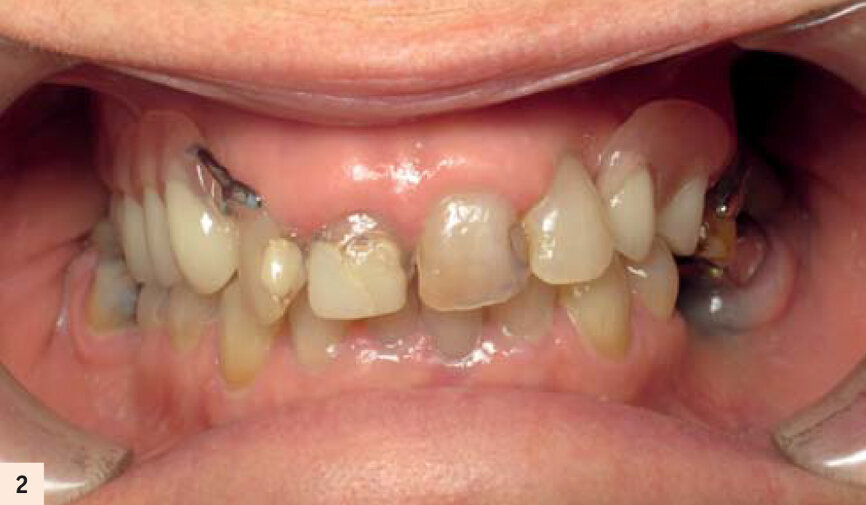

Elle porte un appareil amovible au maxillaire, côtoyant 5 dents naturelles. Elle souhaite une solution fixe (Figs. 1, 2, 3). Après empreintes, mise en articulateur et confection d’un guide radiologique, un examen 3D est réalisé. L’analyse des fichiers DICOM’s transférés sur le logiciel de planification CoDiagnostiX, confirme un faible volume osseux.5Les sinus ont fortement pneumatisé le maxillaire et les parois antérieures sont au niveau des canines.

Radiographie panoramique de la situation initiale.